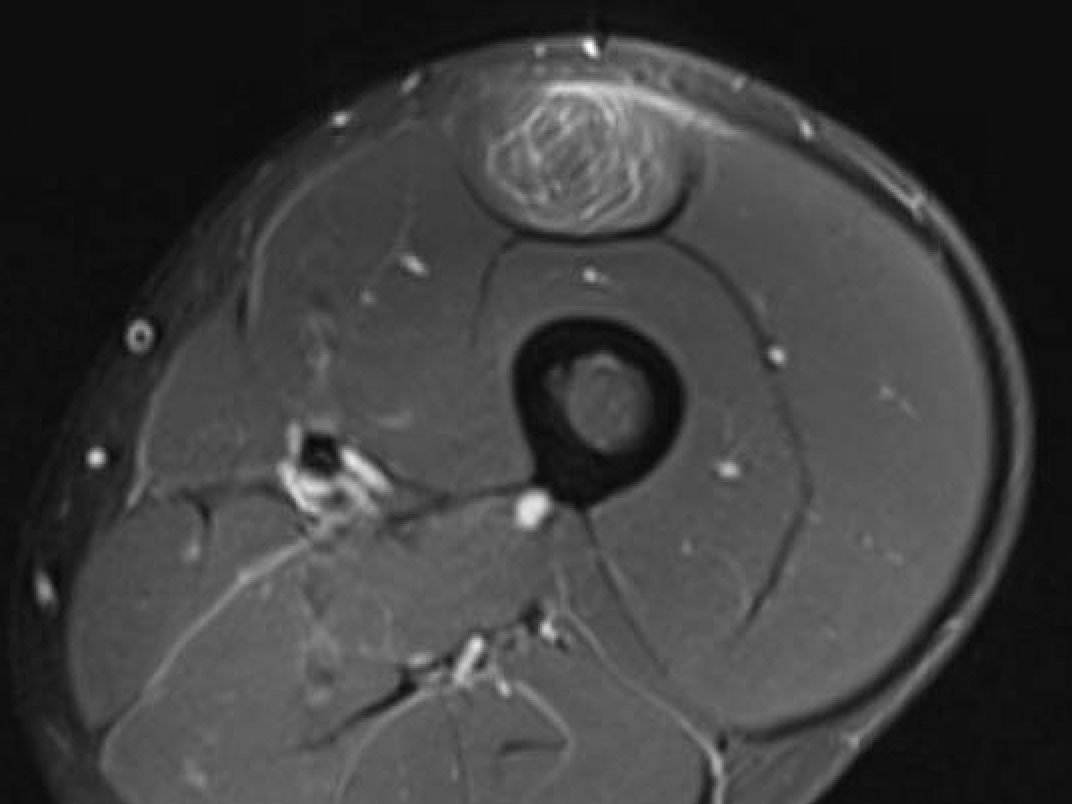

Grade 3C proximal central tendon rectus femoris